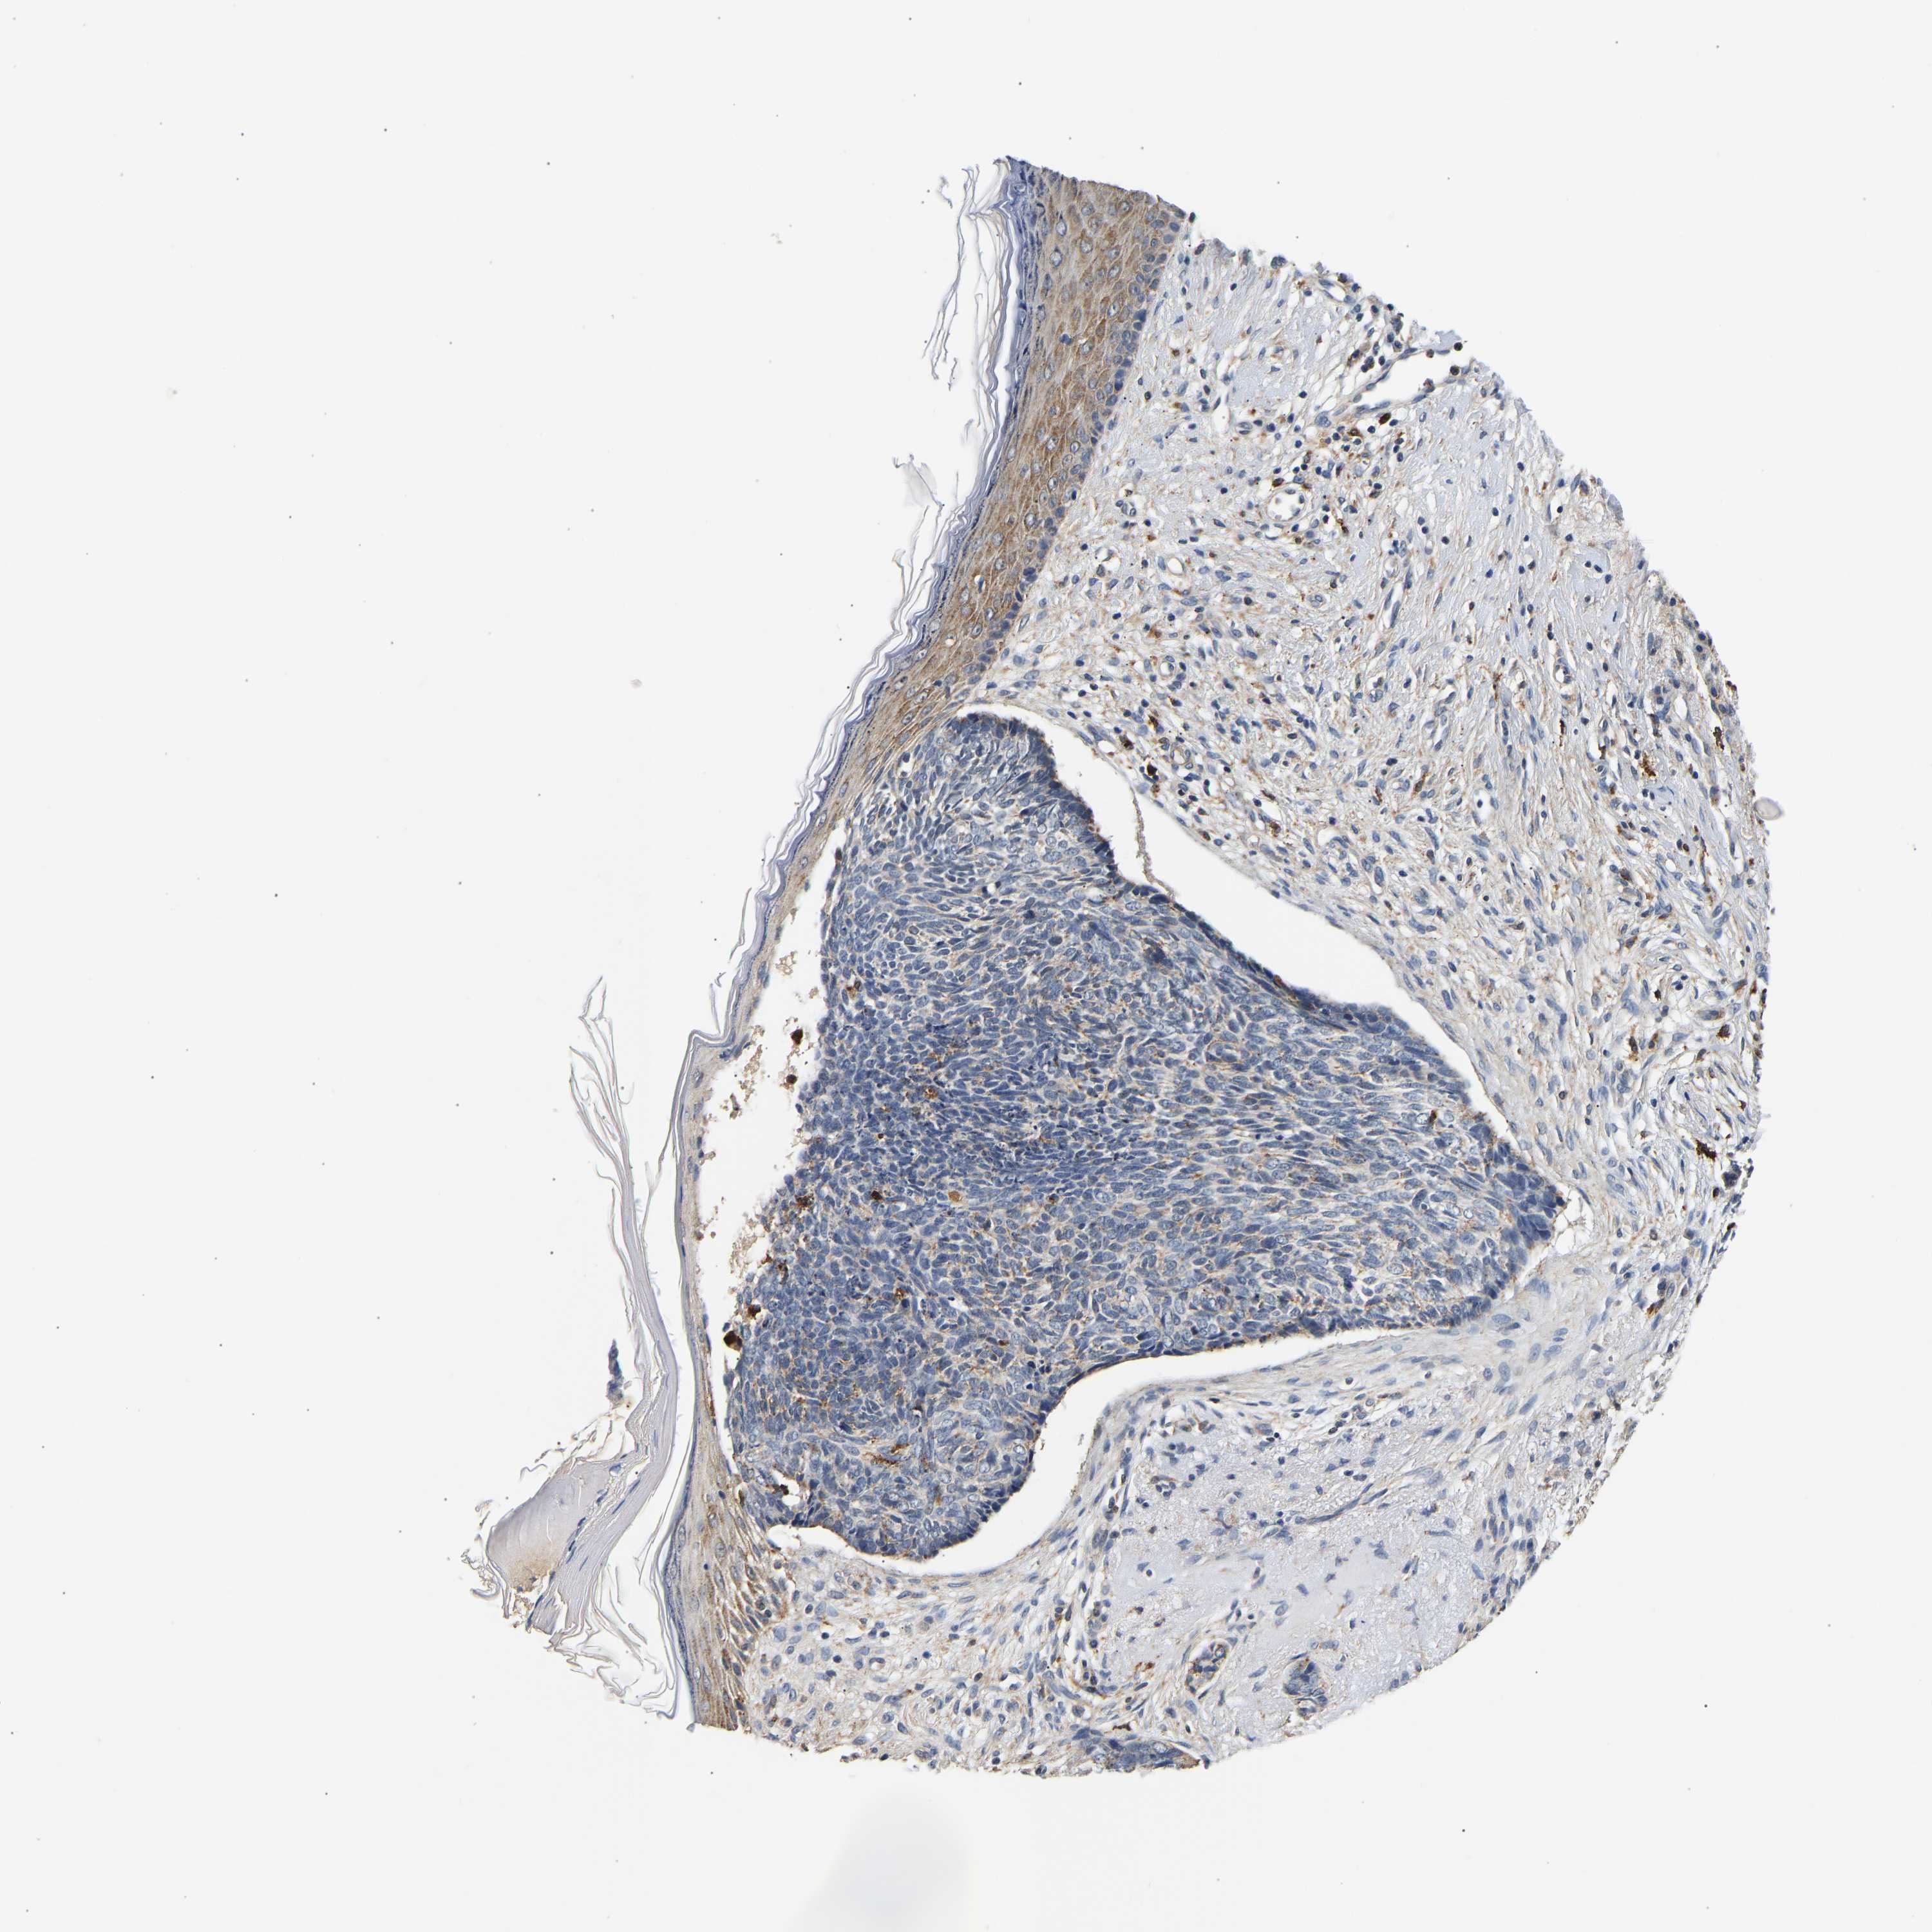

Basal cell and squamous cell cancer

SKIN CANCER - Protein expressioni

A mouse-over function shows sample information and annotation data. Click on an image to view it in a full screen mode. Samples can be filtered based on level of antibody staining by selecting one or several of the following categories: high, medium, low and not detected. The assay and annotation is described here.

Antibody stainingi

Antibody staining in the annotated cell types in the current human tissue is reported as not detected, low, medium, or high, based on conventional immunohistochemistry profiling in selected tissues. This score is based on the combination of the staining intensity and fraction of stained cells.

Each image is clickable and will lead to virtual microscopy that enables deeper exploration of all samples and also displays staining intensity scores, fraction scores and subcellular localization as well as patient and tissue information for each sample.

Antibody HPA019708

Staining

High

Medium

Low

Not detected

Intensity

Strong

Moderate

Weak

Negative

Quantity

>75%

75%-25%

<25%

None

Location

Nuclear

Cytoplasmic/membranous

Cytoplasmic/membranous,nuclear

Basal cell carcinoma